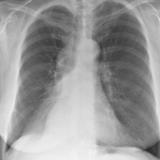

RLL Collapse 1 PA

Date: 02/28/2004

Views: 3360